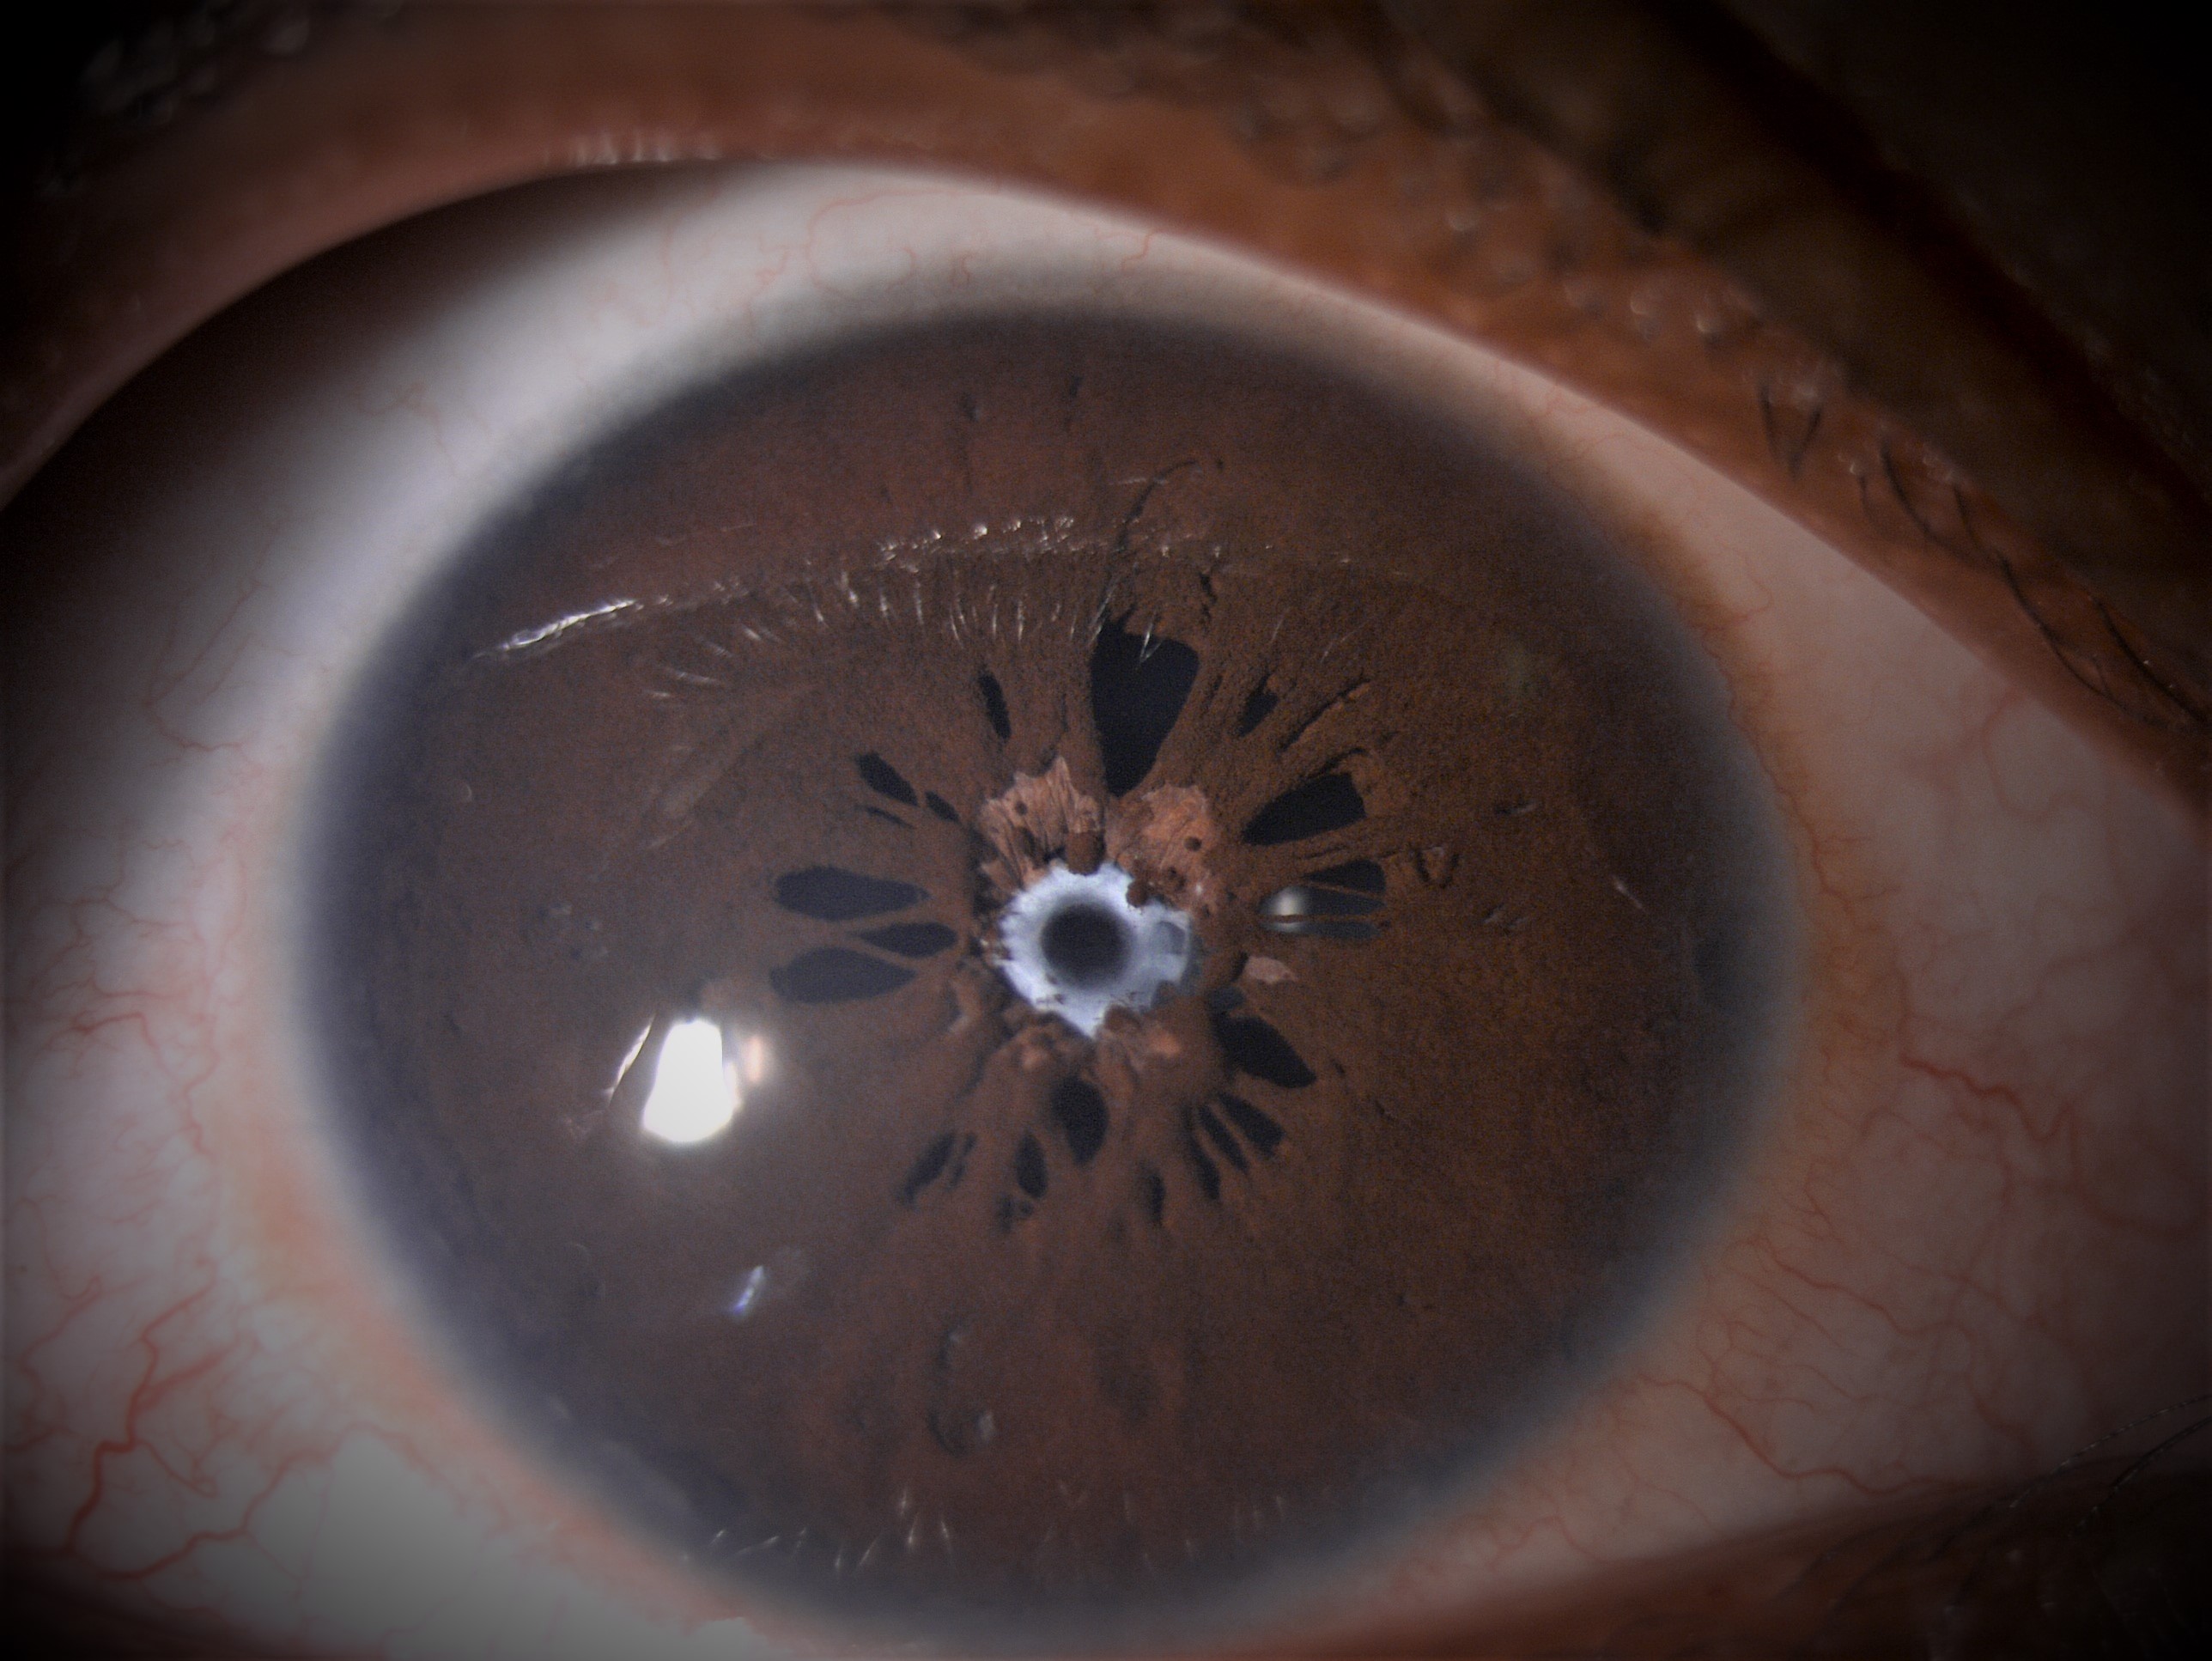

Persistent Pupillary Membrane

Persistent pupillary membrane(PPM) is a frequently encountered congenital anomaly. It represents remnants of anterior tunica vasculosa lentis and appears as strands of connective tissue bridging the pupillary area. They are usually asymptomatic and of no functional significance. In rare cases, dense membranes can persist and obscure the pupil, causing amblyopia.

Slit lamp appearance of PPM can be variable. Most of the times, it can be seen as single or several lacy strands that partially bridge the pupil. The peripheral portion always inserts into the iris collarette. The central portion may attach to the anterior lens capsule or float with free edges. Iris melanocytes may be observed on the anterior lens capsule forming "pigment stars" or "chicken tracks". Infrequently, extensive sheet of iris membrane occluding the pupil may occur.Rare cases of hyphaema from a strand of PPM have been reported.Rarely, progressive pupillary occlusion may be seen with late angle closure glaucoma.